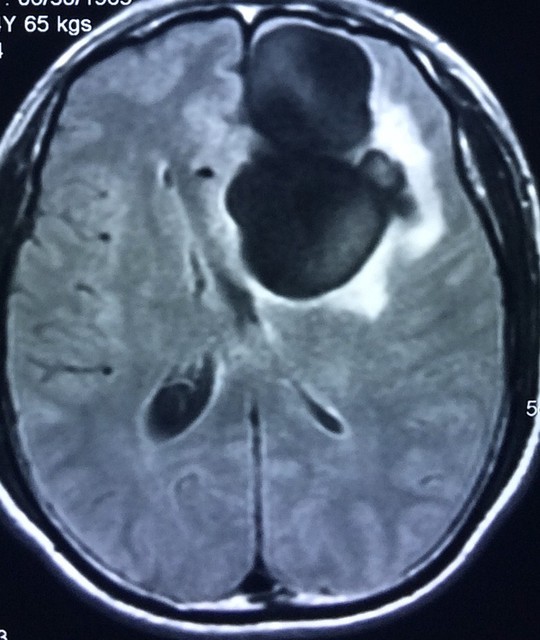

Hình ảnh tổ sán “ăn” một phần trong não – Ảnh: Bác sĩ cung cấp

Trước đó khoảng 2 tuần, bệnh nhân vốn luôn “khoá khẩu” món tiết canh có dấu hiệu đau đầu, choáng váng, sốt, lên cơn co giật. “Tại thời điểm nhập viện, bệnh nhân hôn mê. Kết quả chụp cắt lớp vi tính phát hiện bệnh nhân có một khối u lớn trong não dạng nang, nghi ngờ trong não có nang sán hoặc khối u. Với những bệnh nhân tỉnh táo, bác sĩ sẽ chụp cộng hưởng từ để đánh giá kết quả chính xác hơn nhưng do bệnh nhân đã hôn mê nên được chỉ định mổ ngay lập tức. Kết quả, khi mổ ra các bác sĩ phát hiện một tổ nang sán lớn như chùm nho có kích thước 5 cm x 6 cm làm tổ trong não. Sau mổ, bệnh nhân phải hồi sức 3 ngày mới tỉnh trở lại và được điều trị tích cực” – bác sĩ Liên nói.